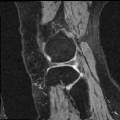

We applied AutoReg to a wide range of MRI registration scenarios from mono-modality (registering brain T1 images to an averaged T1 template, brain T1 to T1 images, brain T2 to T2 images, knee T1 to T1 images, and lung CT inspiration to expiration images) to multi-modality (registering brain T1 to T2 images, brain T2 to T1 images).

Knee T1-to-T1 registration. We employ knee MRIs from the Osteoarthritis Initiative 444https://nda.nih.gov/oai/ with corresponding segmentations of femur and tibia as well as femoral and tibial cartilage [49]. We divide images into 377, 21 and 130 volumes for training, validation and testing. All images are resampled to isotropic spacing of 1mm, in size of .

Table. IX demonstrates performance in terms of Dice score on challenging registration tasks, including brain T1 MR image-to-image, brain T2 MR image-to-image, multi-modal (including T1-to-T2 and T2-to-T1), and knee T1 MR image-to-image registrations. While our method gives an obvious lower variance with a comparable Dice for all of these cases. Fig. 6 depicts the stability of the methods in view of the box-plot of Dice score, where fewer outliers and lower variance indicate a more stable registration. Note that, the optimization-based methods perform slightly better for the brain registration where the image pairs are much more similar to each other. However, they are less satisfying in the knee T1-to-T1 registration. When faced with such various challenging cases, learning-based models struggle to provide comprehensive solutions. While our method gives an obvious lower variance with a comparable mean of Dice for all these cases, showing stronger stability.

Our representative registration results are given in Fig. 7 and Fig. 8. The first three registration cases in Fig. 7 contain image-to-atlas on T1 brain MR, image-to-image on T1 brain MR and T2 brain MR test pairs. The large deformations in scans make registration challenging and difficult. As a result, all the source images are well aligned to the target. The second three rows in Fig. 8 contain knee T1 MR data, multi-modal data, and lung CT inspiration-expiration images. Although large deformations and intensity differences exist in scans, source images are well aligned to the target, demonstrating our outstanding performance.